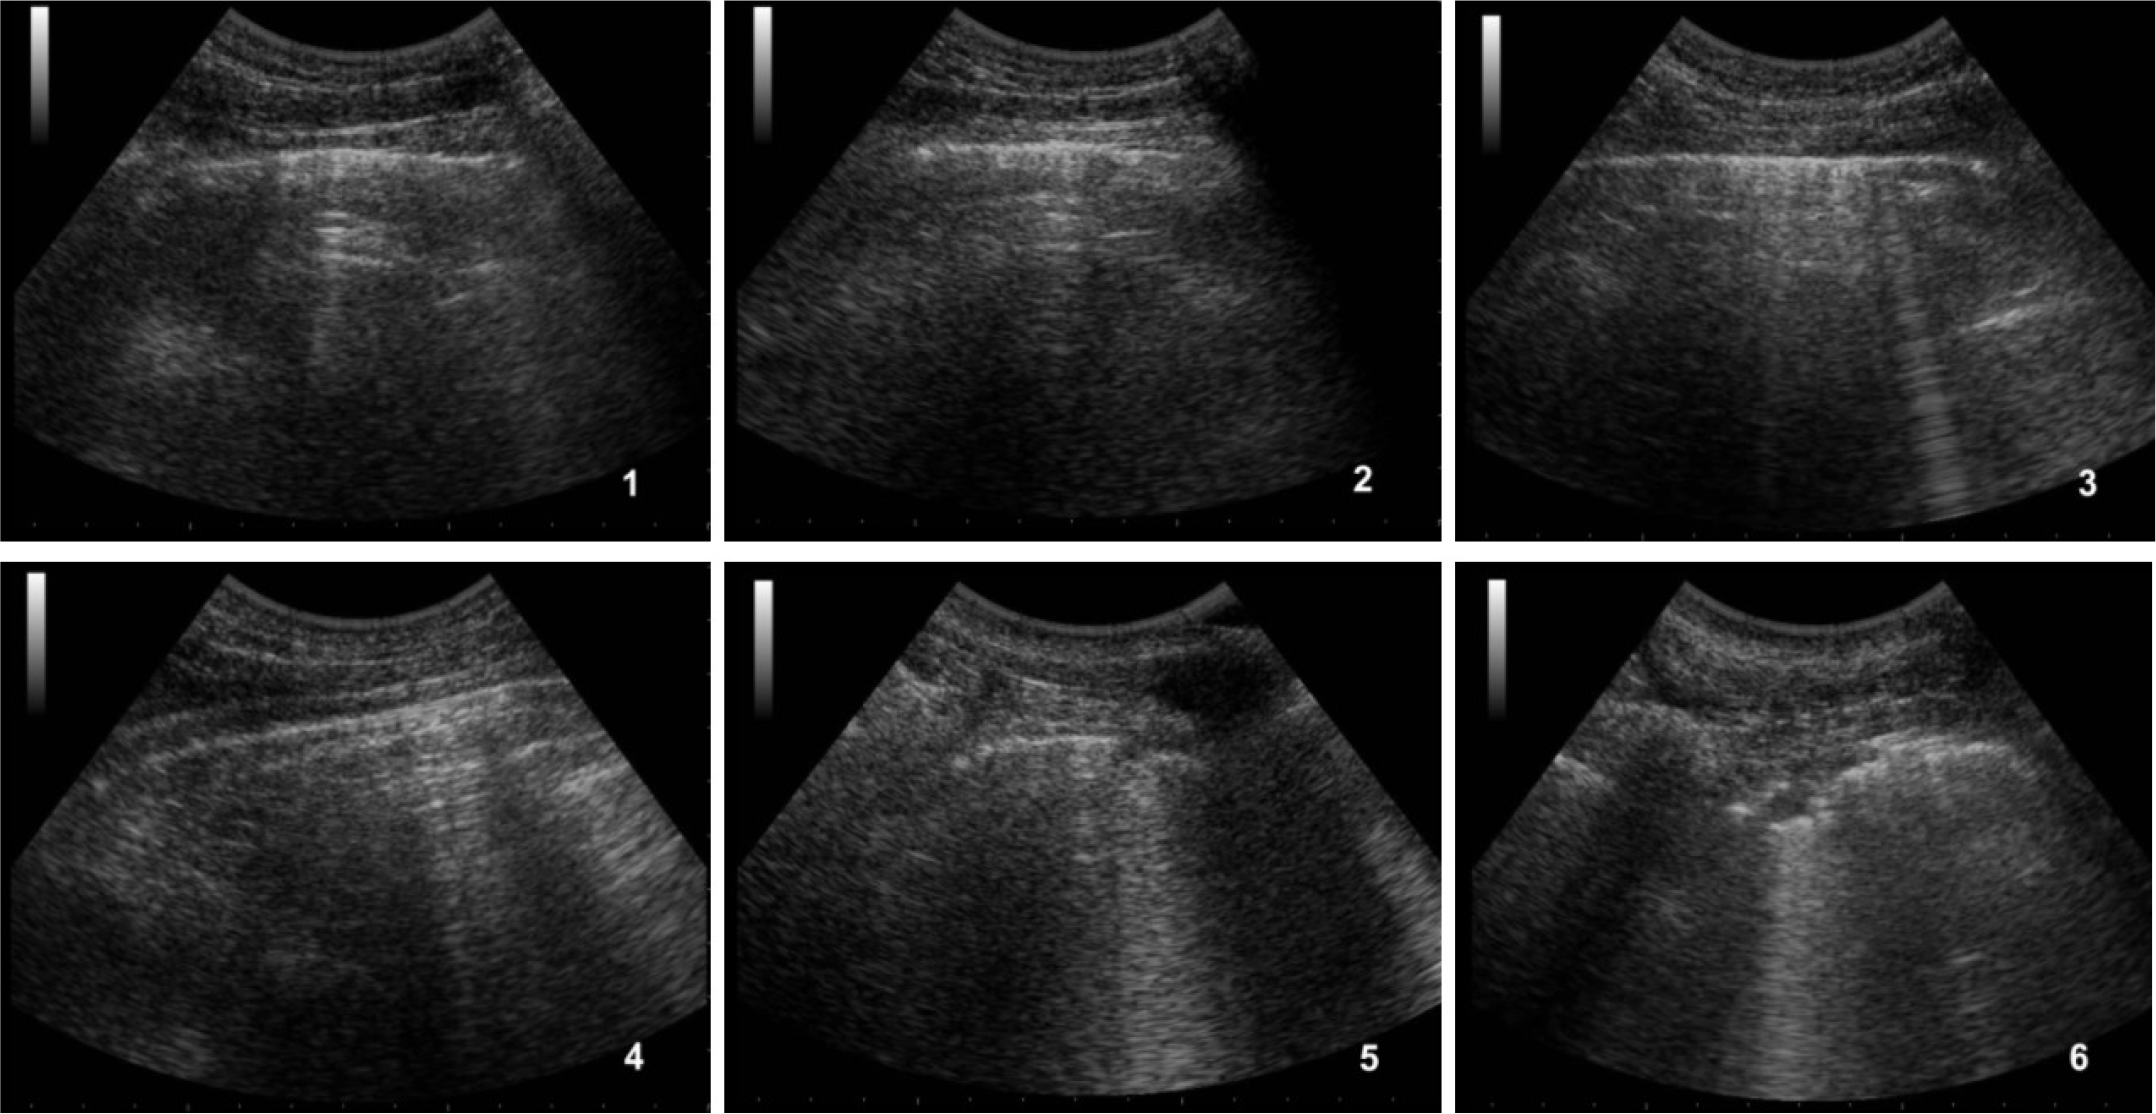

Lung ultrasound showed a suggestive pattern of interstitial lung disease associated with bilateral subpleural consolidations in the postero-inferior scans (Figure 1, 2). The total Lung Ultrasound Score (LUS) was 10. Chest x-ray, performed at the admission, showed a mild thickening of the peribronchovascular interstitium with focal areas of consolidation in the right medio-superior and left medio-inferior regions, compatible with a viral interstitial pneumonia (Figure 3).

Figure 1: Ultrasound of the right lung.

1) antero-superior field with A-lines, 2) antero-inferior field with A-lines, 3) lateral-superior field with A-lines and few B-lines, 4) lateral-inferior field with A-lines, 5) postero-superior field with a small subpleural consolidation and B-lines, 6) postero-inferior field with subpleural consolidation.